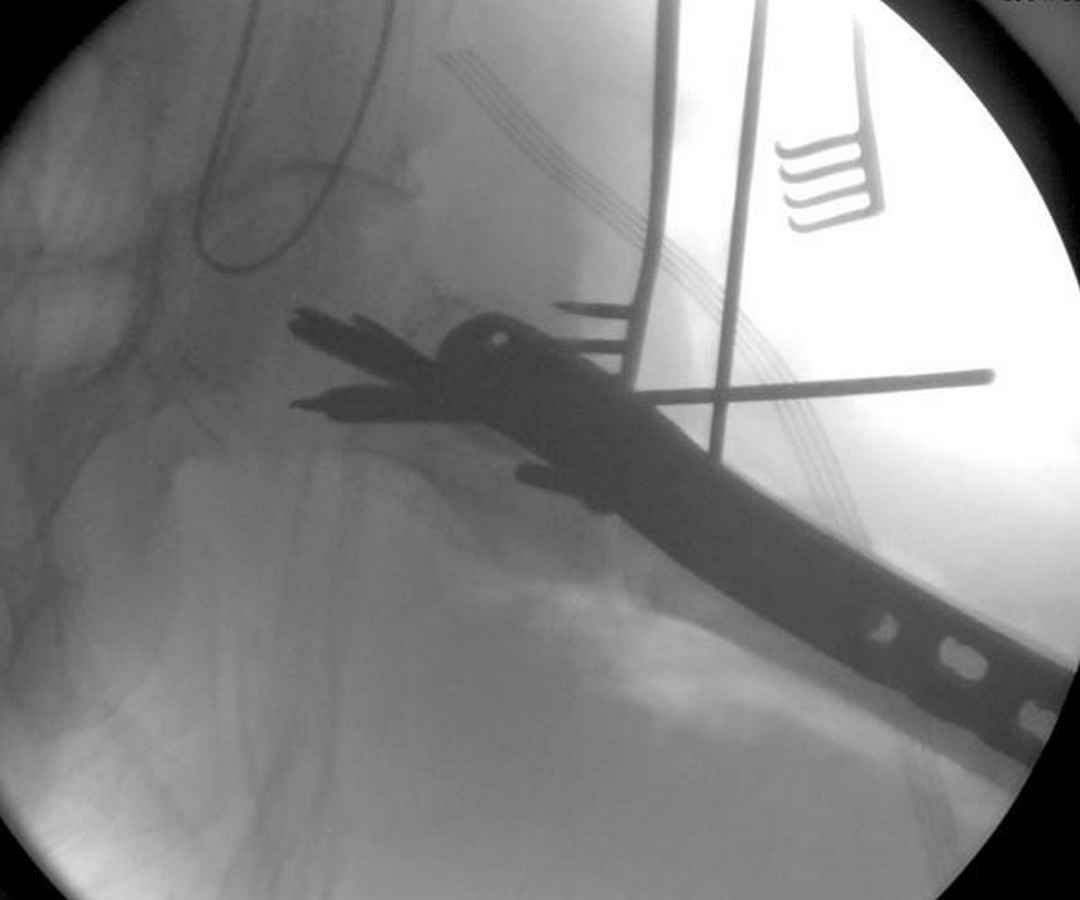

Здесь 83 года, травма в результате падения

Djoldas Kuldjanov, M.D.

Department of Orthopedic Surgery

St. Louis University